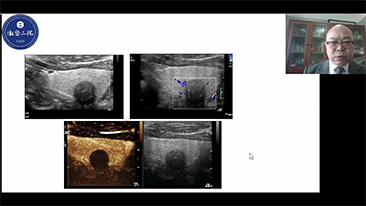

Per le lesioni focali epatiche, come l'emangioma o il tumore al fegato, l'imaging di contrasto a ultrasuoni svolge un ruolo importante. La tecnologia di imaging di contrasto Ultra-wideband non-linear UWN+ consente di ottenere una migliore penetrazione, un rapporto contrasto-tessuto pi├╣ elevato con un indice meccanico pi├╣ basso e un'osservazione del tempo di perfusione pi├╣ lunga.